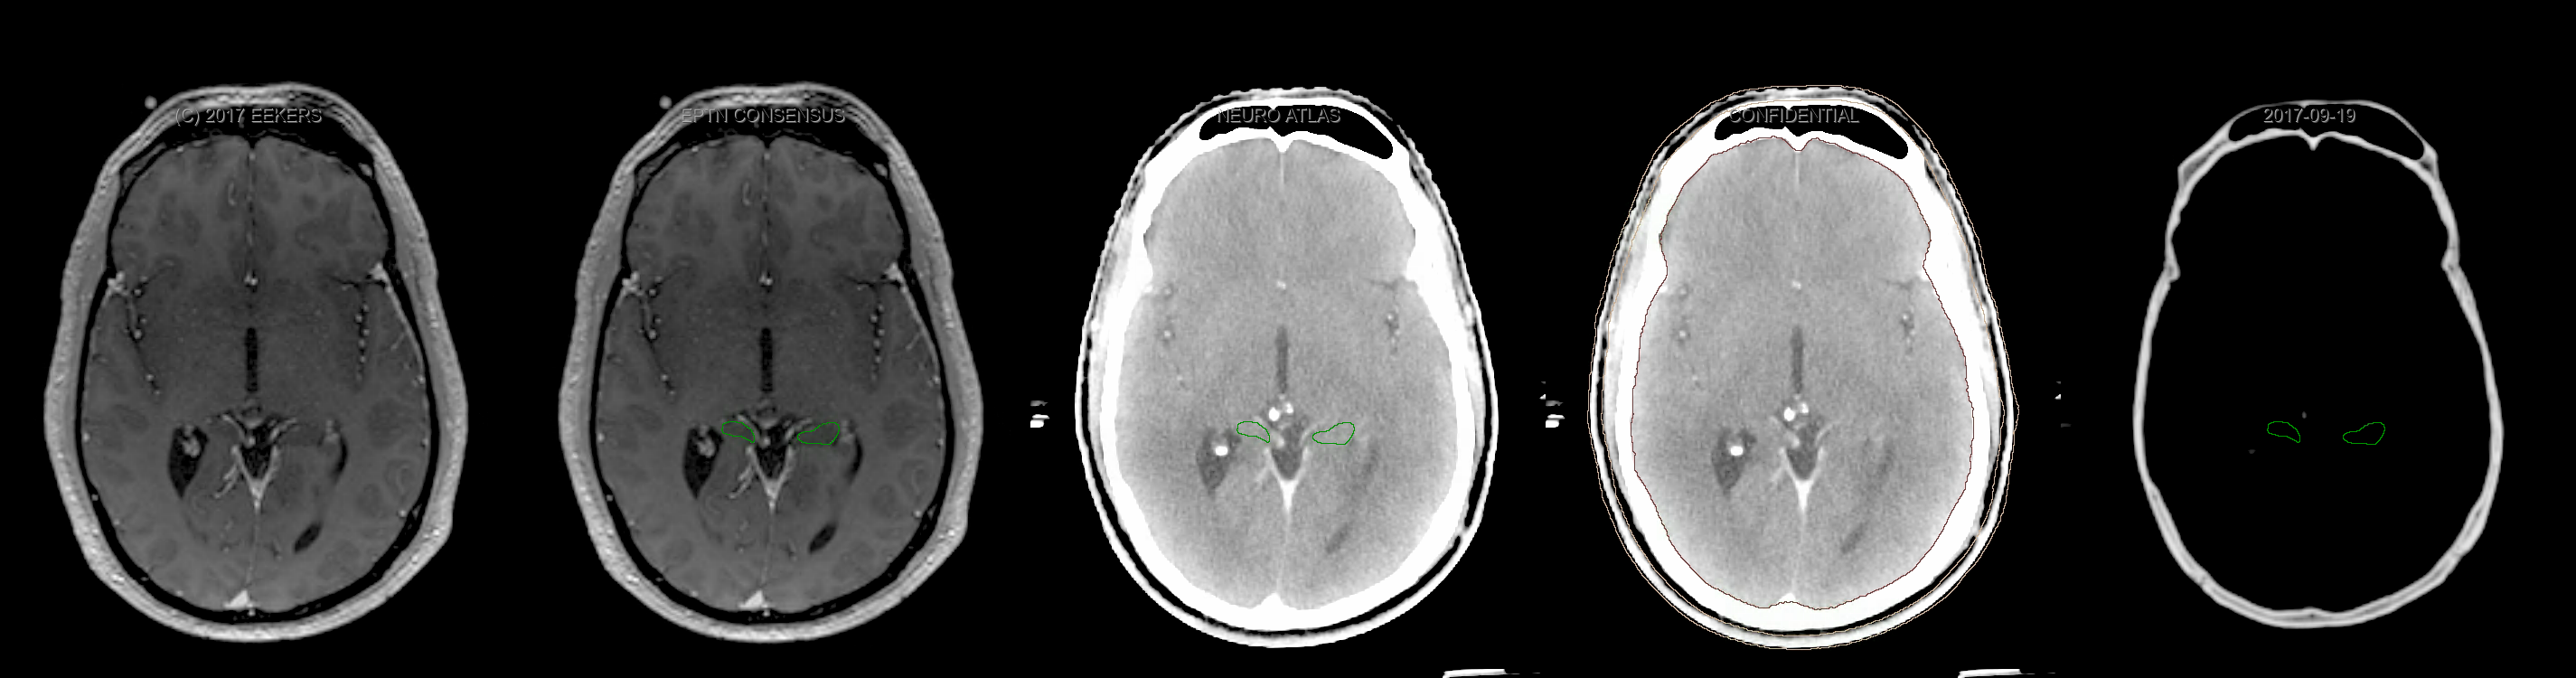

Eekers et al. have published an international neurological atlas for contouring of organs at risk in consensus with the European Particle Therapy Network (EPTN). The purpose of this consensus atlas is to decrease inter- and intra-observer variability in delineating OARs relevant for neuro-oncology. We propose this atlas is used in photon and particle therapy in order to derive consistent dosimetric data. When required this atlas will be updated according to new insights.

Included are all OARs known to be relevant for radiation-induced toxicity in neuro-oncology: brain, brainstem, cochlea, vestibulum & semicircular canals, cornea, lens, retina, lacrimal gland, optic nerve, chiasm, pituitary, hippocampus and skin. A new OAR relevant for neuro-cognition, the posterior cerebellum is also included.

Three-dimensional delineation of the fifteen consensus OARs for neuro-oncology are shown on CT and 3 Tesla (3T) MR images (slice thickness 1 mm with intravenous contrast agent). All are presented in transversal, sagittal and coronal view.

From left to right: MR without structures, MR with structures, CT (WW/WL 120/40) with structures, CT (WW/WL 120/40) with Brain and Brainstem Surface, CT (WW/WL 1500/120)with structures